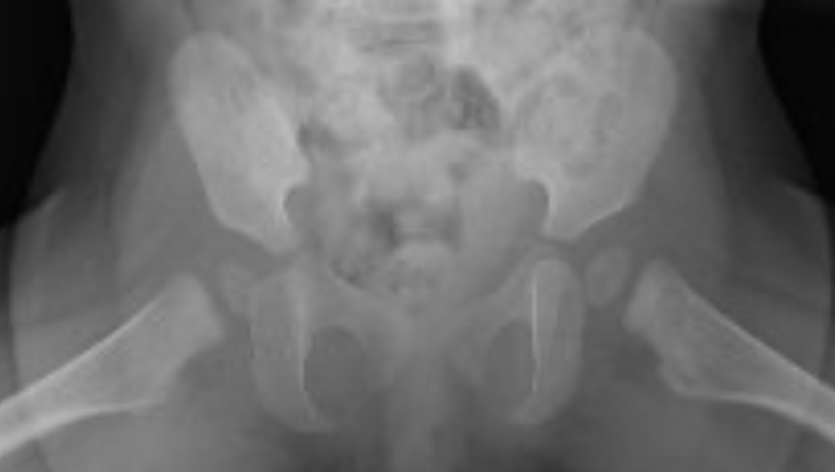

Durante este tiempo, no pudieron atender un problema muy importante: mi displasia en el desarrollo de la cadera bilateral, con ángulos acetabulares aumentados. Este diagnóstico significa que necesito un aparato ortopédico tipo Calot que usaré por 4 meses además de la rehabilitación después de mi aparato para corregir los ángulos de mi cadera. Sin este dispositivo, no solo tendré dificultades para caminar, sino que también podría necesitar una operación en un futuro cercano.